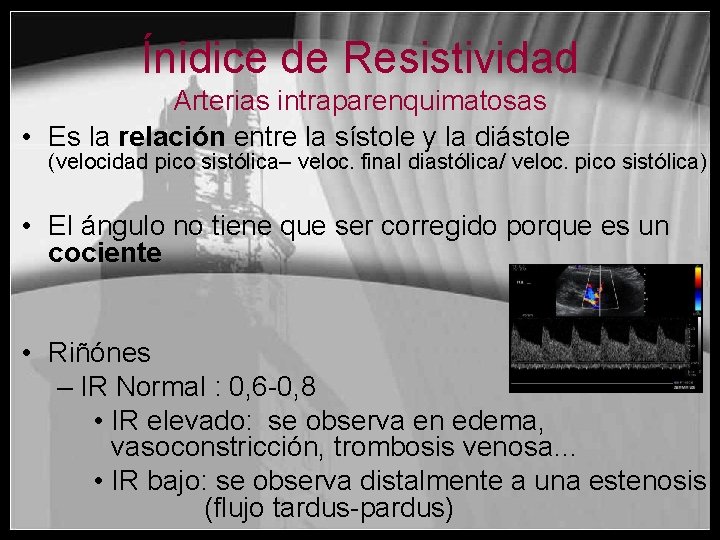

Ínidice de Resistividad Arterias intraparenquimatosas • Es la relación entre la sístole y la diástole (velocidad pico sistólica– veloc. final diastólica/ veloc. pico sistólica) • El ángulo no tiene que ser corregido porque es un cociente • Riñónes – IR Normal : 0, 6 -0, 8 • IR elevado: se observa en edema, vasoconstricción, trombosis venosa… • IR bajo: se observa distalmente a una estenosis (flujo tardus-pardus)